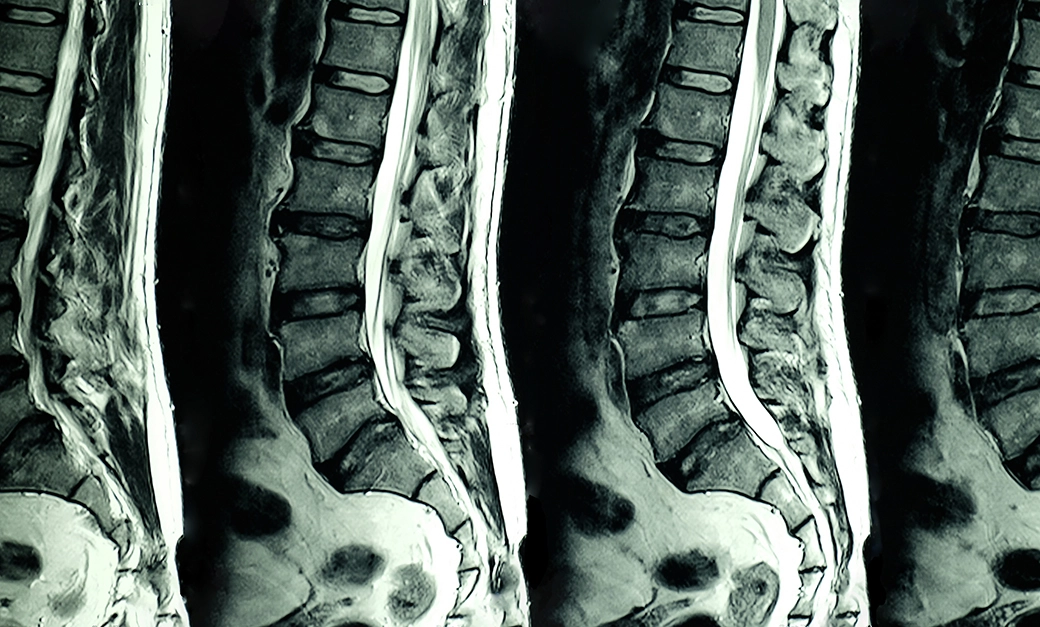

DDD is a progressive illness affecting the discs of your spine. Common non-invasive means to help cure degenerative disc disease include:

In a nutshell, degenerative disc disease involves the degradation of the spine, its vertebrae, and the discs that make it up. Anything that contributes to the health of those parts of the body or inhibits their continued decay will help cure degenerative disc disease (DDD). As a rule, chiropractic care is excellent for the health of the spine and its constituent parts.